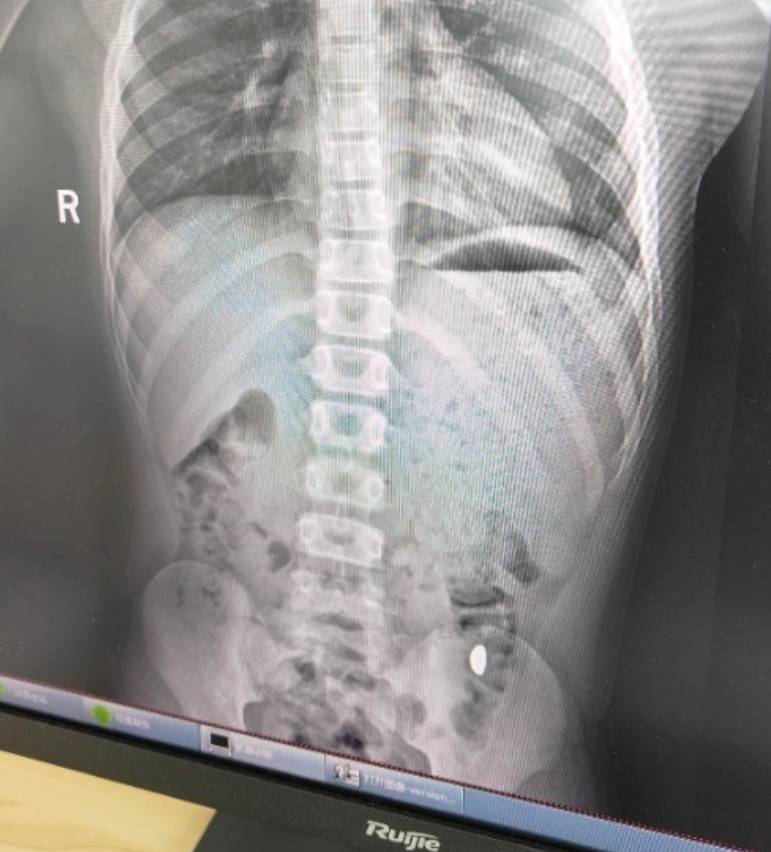

右下加亮点为金豆比特儿海外交易平台。